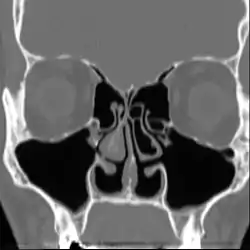

لا توجد نتائج فحص بدني موضوعية تشخص متلازمة الأنف الفارغة بصورة أكيدة،[1] فقد ينقص أو يغيب واحد أو أكثر من المحارات عند مشاهدتها في التصوير الطبي أو من خلال المنظار الداخلي دون أي علامة على وجود انسداد أنفي، ويكون الغشاء المخاطي جافًا وباهتًا، وقد تكون هناك علامات على عدوى ثانوية.[1]

لا توجد معايير توافقية لتشخيص المتلازمة، وعادة ما يتم تشخيصها عن طريق استبعاد الحالات الأخرى مع وجود العلامات والأعراض،[1][2][3] وقد تم اقتراح "اختبار القطنة"، حيث يتم وضع قطنة رطبة في المكان الذي يجب أن تكون فيه المحارة لمعرفة ما إذا كان ذلك يعمل على تخفيف الحالة. وقد يكون ذلك الاختبار مفيدا في التعرف على الأشخاص الذين قد يستفيدون من الجراحة، في حين أنه لم يتم التحقق منه كما أنه غير مقبول على نطاق واسع.[1][2][3]